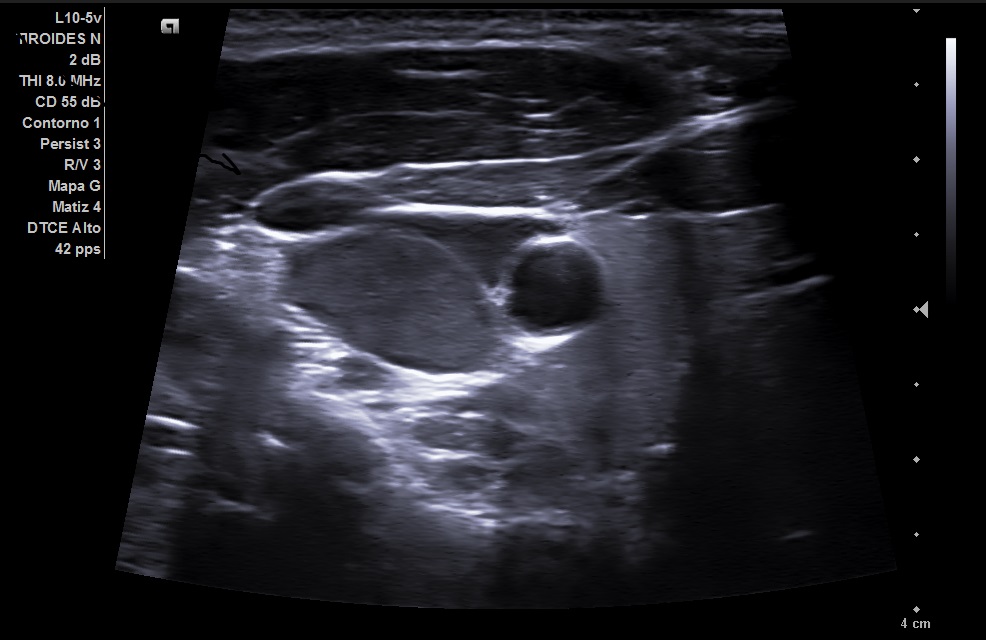

Se realizó en consulta una ecografia clínica, se colocó al paciente decúbito supino con ligera hiperextensión del cuello y tras palpar el bultoma se localizó con la sonda. Visualizamos en nivel 1 una imagen hipoecogénica ovalada de 22 mm con alteración de la estructura pero con hilio graso conservado y con aumento de vascularización compatible con adenopatía reactiva.